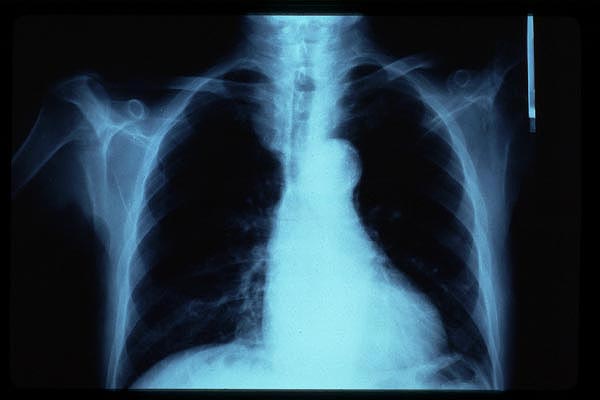

Cardiomegalia. ICC.

Marcapasos

Cardiomegalia.